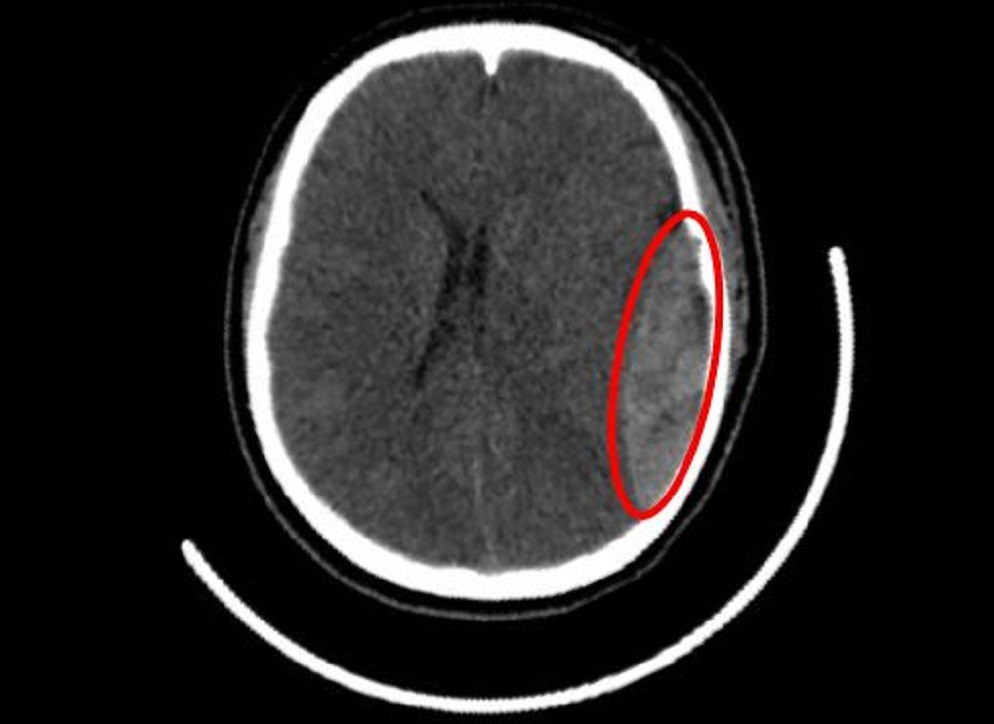

Hình ảnh kiểm tra vị trí chấn thương sọ não của nữ sinh

Kết quả chẩn đoán hình ảnh và mức độ tổn thương

Sau khi tiến hành chụp CT scan não bộ, kết quả cho thấy vùng hộp sọ bên phải xuất hiện vết nứt sâu kèm theo máu tụ ngoài màng cứng tạo áp lực lên mô não xung quanh. Đây là một trường hợp chấn thương sọ não phức tạp cần can thiệp ngoại khoa ngay lập tức để ngăn ngừa triệu chứng thần kinh xấu đi.

Các bác sĩ chuyên khoa thần kinh đã tiến hành phẫu thuật khẩn cấp để loại bỏ khối máu tụ ngoài màng cứng, đồng thời xử lý vùng hộp sọ bị tổn thương nhằm giảm áp lực cho não bộ. Ca mổ diễn ra suôn sẻ và thành công ngoài mong đợi. Sau hơn một tuần điều trị tích cực tại phòng chăm sóc đặc biệt, sức khỏe của nữ sinh dần ổn định với khả năng phục hồi tốt mà không để lại di chứng nào đáng kể.